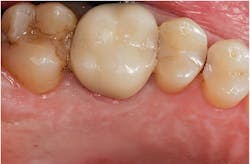

Figure 1: A patient presented for a new-patient examination. During the appointment, radiographic decay was noted on Nos. 12, 13, and 15. Treatment plan options were given to the patient. The patient elected to have Nos. 13 and 15 crowned and to have No. 12 restored with a new composite filling.

Figure 2: Intraoral images were shown to the patient, and it was explained that the existing crown on No. 14 (done several years ago) would not esthetically match the newly restored teeth. Also, the anatomical contours of the new porcelain restorations would be less ideal, due to the anatomy of the existing crown. Doing all three porcelain restorations at the same time would allow the contacts to be made more ideal and the crowns made to look similar. The patient elected to have all of the restorations in the quadrant completed during the same visit.